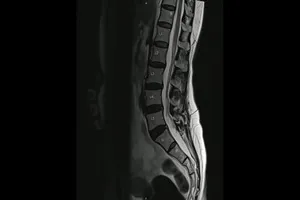

MRI(자기 공명영상) 검사는 강력한 자기장과 라디오파를 이용해 우리 몸속을 생생하게 들여다보는 최첨단 영상 검사입니다. 뇌, 척수, 관절 등 다양한 부위의 질환을 조기에 발견하고 정확하게 진단하는 데 필수적입니다.

MRI 검사는 CT 검사보다 훨씬 더 세밀한 영상을 제공하여, 마치 우리 몸의 지도를 보듯이 각 조직과 기관의 미세한 차이까지 파악할 수 있습니다. 뇌종양, 뇌출혈, 척추 디스크, 관절염 등 다양한 질환의 정확한 위치와 크기를 정밀하게 확인하여, 환자에게 꼭 맞는 최적의 치료 계획을 세우는 데 결정적인 역할을 합니다.

2. 척추 질환

· 허리 디스크, 목 디스크

척추뼈 사이의 디스크가 튀어나와 신경을 압박하는 질환으로, MRI 검사를 통해 디스크의 위치와 정도를 확인하고 치료 계획을 세웁니다.

· 척추 협착증

척추관이 좁아져 신경이 압박되는 질환으로, MRI 검사를 통해 협착된 부위를 확인하고 치료 방법을 결정합니다.

· 척추 측만증

척추가 옆으로 휘어진 질환으로, MRI 검사를 통해 척추의 휘어진 정도와 척수 손상 여부를 확인합니다.